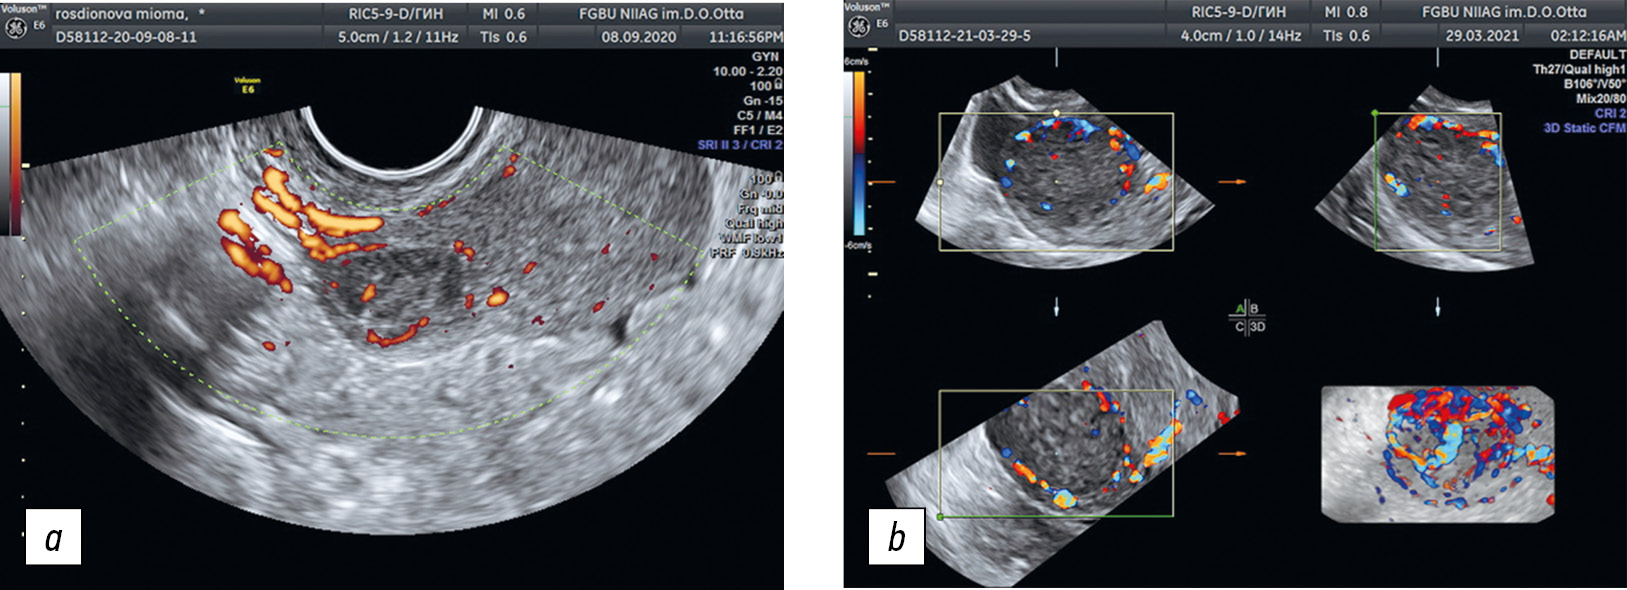

- Оценка васкуляризации миометрия с помощью 3D power Doppler glass body (рис. 5). Для оценки васкуляризации после получения двухмерного изображения матки применена методика 3D power Doppler glass body. Область интереса была расположена таким образом, чтобы туда попадал исследуемый узел и занимал не более половины площади. После этого использована функция glass body, затем — функция 3D. В результате получено объемное изображение матки с сосудами, распределенными вокруг исследуемого очага или проходящими сквозь толщу миометрия. По аналогии со стандартным допплерометрическим исследованием оценен ход сосудов по отношению к обследуемому очагу — для миомы характерно концентрическое расположение сосудов. Если у сосудов нет определенного направления хода, данные расценены как проявление очага аденомиоза. Необходимо отметить, что применение этой методики оценки сосудов становится особенно актуальным при выраженном диффузном аденомиозе, так как на его фоне зачастую снижается васкуляризация, и визуализировать сосуды обычным способом становится крайне сложно.

Рис. 5. Оценка васкуляризации образования: а — энергетическое допплеровское кодирование; b — трехмерная реконструкция в режиме энергетического допплеровского кодирования с использованием методики glass body

Fig. 5. Assessment of the formation vascularization: a, power Doppler; b, 3D power Doppler glass body